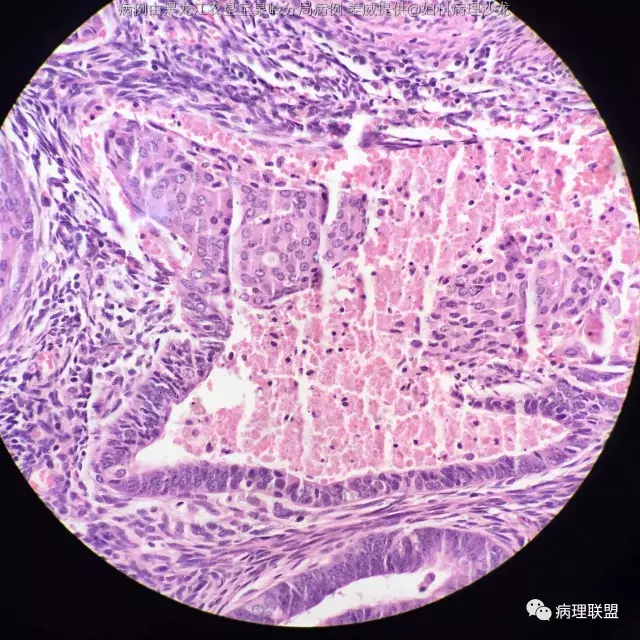

女 45岁,子宫内膜 全切子宫 术前非典(病例由黑龙江农垦宝泉岭分局病理 姜威提供,致谢!)

@黑龙江农垦宝泉岭分局病理 姜威 :子宫内膜样癌伴鳞状分化